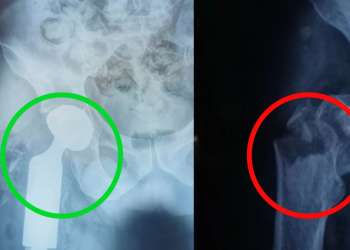

Ciudad de Guatemala, 3 oct (AGN).- El Hospital Nacional de Retalhuleu alcanzó un nuevo hito médico al practicar, con éxito y por primera vez en sus instalaciones, una cirugía de ...